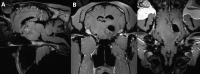

Figure 1.

(A) T2w sagittal, (B) T2w transverse and (C) T1w 3D reconstructable magnetization-prepared gradient-echo (MP-RAGE) with contrast medium (gadoteric acid, clariscan TM, GE Healthcare AG, opfikon, Switzerland) dorsal magnetic resonance images of the head of a 16-year-old warmblood mare, depicting a large well-delineated pituitary macroadenoma compressing the thalamus, the midbrain, and the optic chiasm.